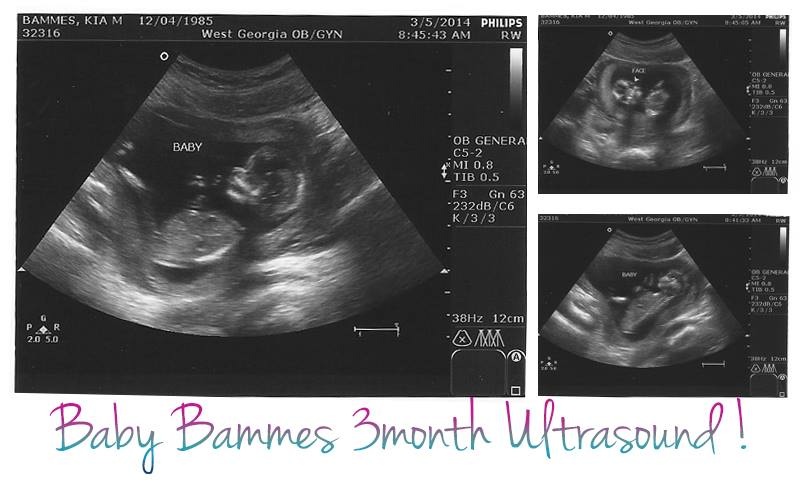

Hi,

Expecting my first child in August. These are my only ultrasound pics so I'm hoping you guys can help me predict the gender via nub or skull theory. Please share your guesses and why you chose B or G. I'm trying to sharpen my prediction skills. Thanks in advance!

Attachment 17449